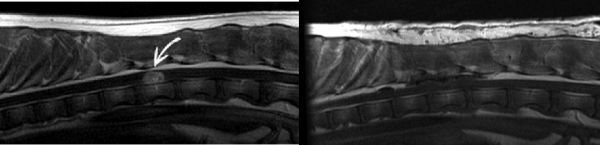

图4 是18个月大的哈士奇犬雄性。MR!图像显示T12椎体节段水平的局灶性、边界清楚、左侧、对比增强、硬膜内/髓外脊髓肿块。当肿瘤位于硬膜内和髓外时,意味着它位于硬脑膜(脊髓的覆盖物)中,但不在脊髓组织中。在肿块周围的区域有脊髓肿胀。硬膜内/髓外脊柱肿块只有少数几种类型。脑膜瘤是该部位最常见的肿瘤。周围神经鞘瘤、肉芽肿和出血也可以在这里找到。但还要注意一种称为肾母细胞瘤的肿瘤,因为这些肿瘤通常是硬膜内/髓外的,好发于年轻大型犬的胸腰椎区域。主人选择手术切除(去除)肿块,并进行随后的组织病理学评估以获得明确的诊断。DePompa医生进行了左侧T11-T13半椎板切除术,随后切除了肿块。右图是该哈士奇进行了术后MRI结果表明见肿瘤切除成功。

图5是一种特殊的脊髓肾母细胞瘤,这些细胞在胚胎发生过程中被困在椎管内,随后在生命的某个时间后出现肿瘤行为。动物的脊髓肾母细胞瘤非常罕见。肾母细胞瘤的治疗选择有限,手术减瘤(切除)是兽医学的主要治疗选择。手术后的后续化学和放射治疗被认为是有帮助的。